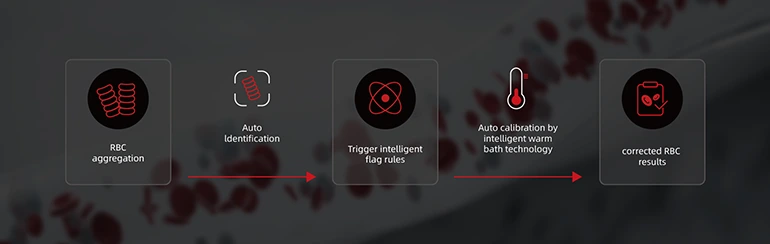

Усовершенствованное решение для защиты от помех для RBC

- Обеспечьте интеллектуальные правила маркировки для агрегации RBC.

- Автоматическая коррекция результатов с помощью технологии «тёплая ванна» уменьшает помехи, вызванные агрегацией RBC.